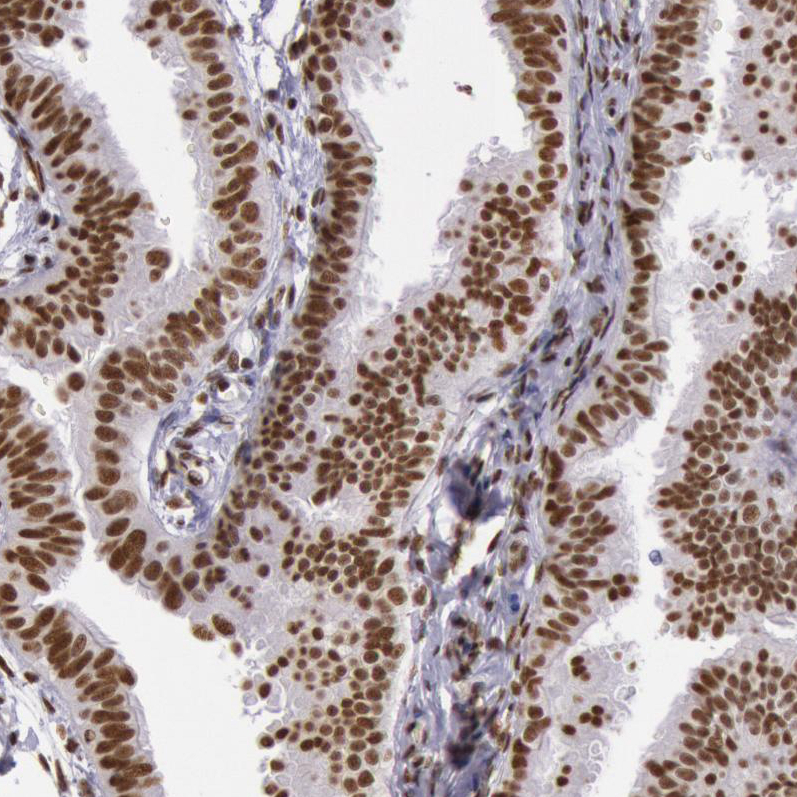

Immunohistochemical staining of human cerebral cortex shows moderate nuclear positivity in neurons.